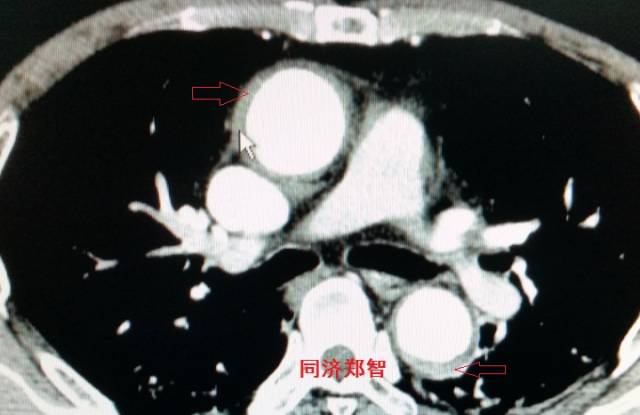

病例二

胸部平扫CT提示升主动脉增宽(红色星形标记),CTA证实A型主动脉夹层伴升主动脉夹层动脉瘤形成。